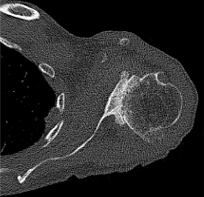

Case two is an 86-year-old female with long standing left shoulder pain and loss of function. Preoperative exam shows 70° of active forward flexion, neutral external rotation, and internal rotation to the lateral thigh. Radiographs (Figure 5) and CT scan (Figure 6) show significant posterior bone loss and retroversion with medialization of the joint line. Options include asymmetric reaming, an augmented component, or bone grafting. An augmented reverse baseplate was selected for this elderly female. Radiographs at six months show a well fixated baseplate with improvement of the pre-operative retroversion (Figure 7).